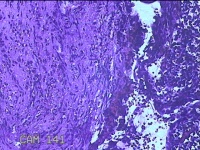

宫颈2点、3点、9点组织

性别

女

年龄

38岁

临床诊断

人乳头瘤病毒感染

一般病史

宫颈其他HPV12阳性

标本名称

大体所见

1.“宫颈2点组织”:灰白粉红色组织0.8x0.5x0.2cm一块。 2.“宫颈3点组织”:灰白粉红色组织0.7x0.5x0.2cm一块。 3.“宫颈9点组织”:灰白粉红色组织0.7x0.5x0.2cm一块。

图2